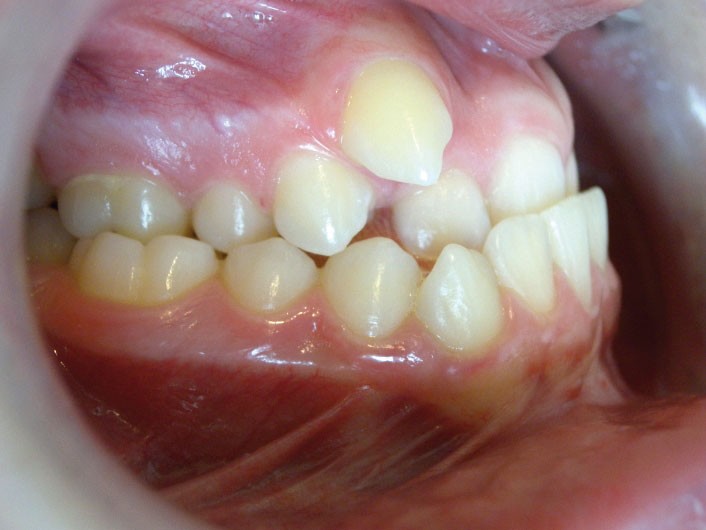

Guillaume, 14 ans, se présente pour la première fois en consultation d’orthodontie, adressé par son dentiste. Il se plaint de la position de ses canines.

Compte tenu du décalage squelettique modéré, (ANB faible (- 3°) néanmoins AoBo (-10,5 mm) est élevé), du menton bien placé sur le plan esthétique, du fait que la rétrocheilie est directement en corrélation avec l’inversé d’articulé, de l’âge du patient (trop important à mon sens pour un masque facial et trop jeune pour proposer directement une chirurgie), il a été choisi de le traiter par disjonction non chirurgicale et multi-attache sans extractions.

Néanmoins, l’interrogation porte sur la stabilité du cas à long terme car l’engrènement n’est pas parfait côté gauche (la stabilité est maintenue trois ans après traitement actif).